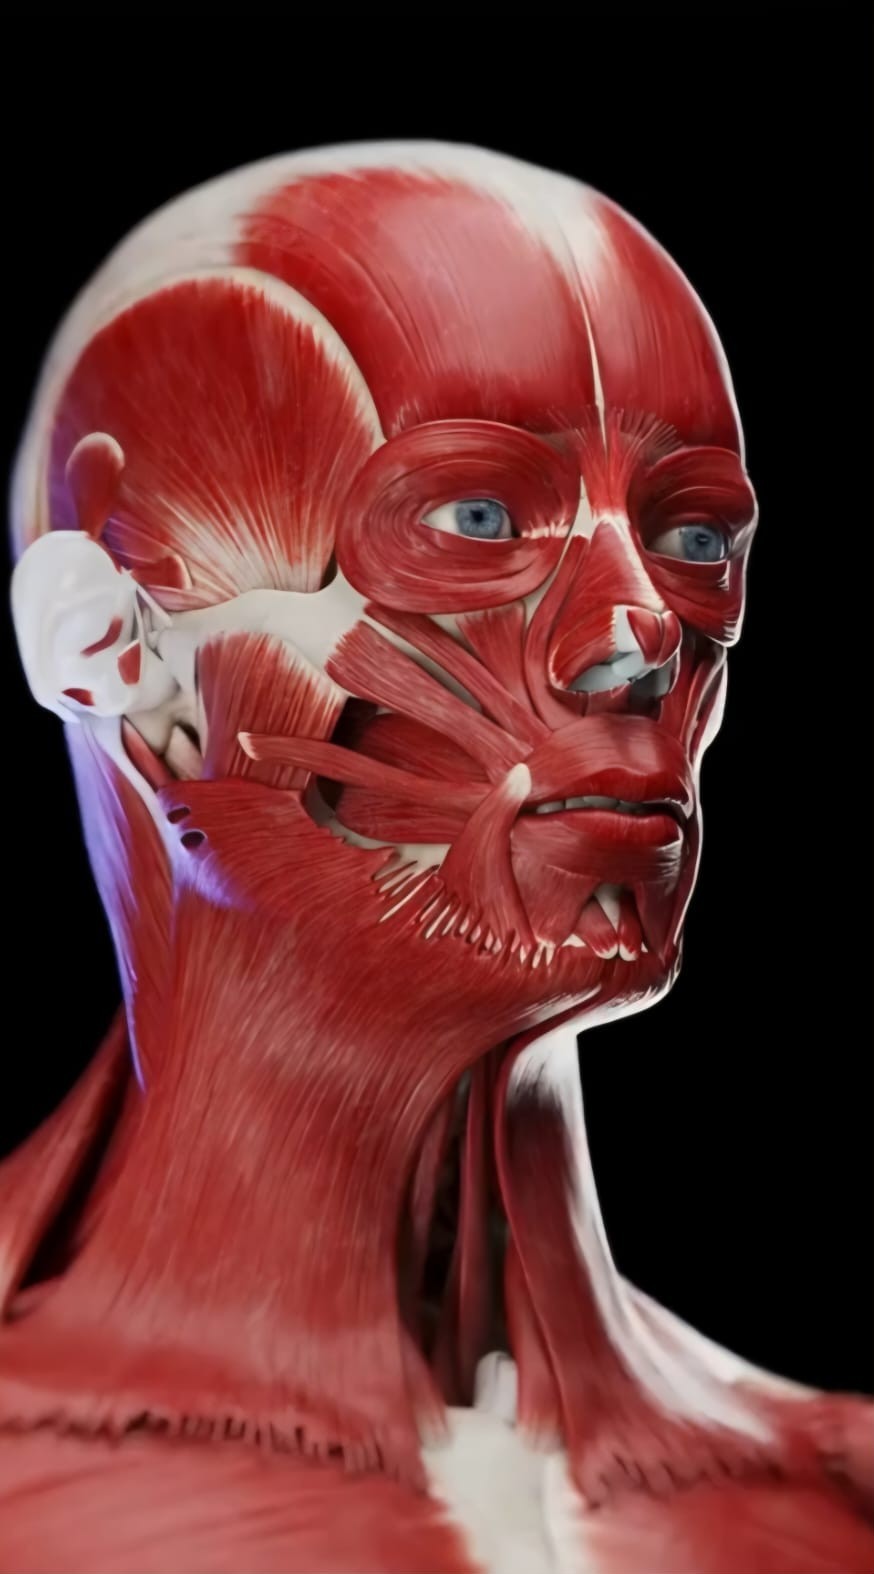

Especialização em Motricidade Orofacial - Edição 2026/2027

- Imagem principal

- DataInício a 10 de Janeiro de 2026 à 07 de Fevereiro de 2027. Carga Horária de 240h Formato - E Learning